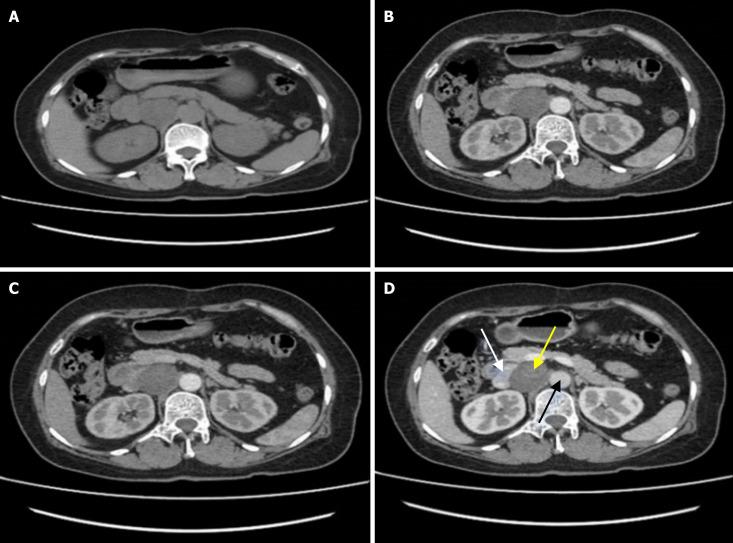

A 56-year-old woman was admitted to the hospital with right upper abdominal discomfort for more than 6 months, experiencing occasional pins and needles sensation and radiation from the right shoulder and back. Prehospital CT of the upper abdomen revealed a retroperitoneal mass suspected to be a retroperitoneal ganglioneuroma. Surgery was recommended, and an enhanced CT scan of the upper abdomen, along with preoperative three-dimensional reconstruction, was performed after admission. The imaging indicated that the mass, measuring approximately 4.1 cm × 3.8 cm × 4.8 cm, was situated between the abdominal aorta and the inferior vena cava, extending downward to the level of the left renal vein. After ruling out any contraindications to surgery, a minimally invasive laparoscopy was performed to excise the mass precisely. The surgery was successful without any postoperative complications, and the 2-month follow-up revealed no abnormal signs of recurrence.

一名56岁女性因右上腹不适6个月以上入院,偶尔有刺痛感,并伴有右肩和背部放射痛。院前上腹部CT显示腹膜后肿块,怀疑为腹膜后神经节瘤。建议手术治疗,入院后进行了上腹部增强CT扫描及术前三维重建。影像学检查显示,肿块大小约为4.1 cm×3.8 cm×4.8 cm,位于腹主动脉和下腔静脉之间,向下延伸至左肾静脉水平。排除手术禁忌证后,进行了微创腹腔镜手术精确切除肿块。手术成功,无术后并发症,2个月随访未发现复发异常迹象。